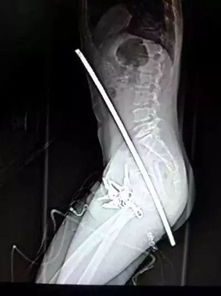

近日日本社交平台上一组“特殊照片”的讨论度远超同期娱乐新闻——22岁演员、写真偶像丰岛心樱分享的胸腔X光片,原本是想展示健康状态,却意外引发了关于“身体轮廓”的全民热议。 作为近年写真圈的“黑马”,丰岛心樱的出道轨迹藏着些“不按常理出牌”的巧合:国中二年级时她抱着“试试而已”的心态报名《Seventeen》杂志模特甄选,虽未拿到名次,却被台下的经纪公司星探相中签约,此后几年她陆续拍过广告、演过小角色,直到2023年登上《周刊Playboy》推出首本写真集,才凭借清透的小鹿眼、利落的肩颈线条和“笑起来像阳光穿过树叶”的元气感彻底“破圈”,成为不少粉丝心中“能把‘日常感’拍出‘杂志感’的神奇存在”,此前她的写真作品多以“校园风”“海边风”为主,每一组都能引发“求原图”的热潮,连杂志编辑都调侃“她的照片自带‘治愈滤镜’”。 而这次让她“火出写真圈”的,是一张体检时拍的胸腔X光片,照片里肺部纹理清晰,没有任何病变迹象,丰岛心樱配文调侃“医生说我的肺比同龄人干净十倍,是不是漂亮得像精心画的素描?”原本是想和粉丝分享“每年坚持体检”的好习惯,却没想到评论区的方向完全“跑偏”:有人放大照片分析“锁骨的线条太优越了,从肩膀到脖子的弧度像用圆规画的”,有人留言“突然觉得X光片也能当‘颜值证明’,这轮廓比我P三天的自拍还好看”,甚至有粉丝开玩笑“以后拍写真不用找摄影师了,直接拿体检报告当素材吧”,不到24小时,相关话题就冲上了日本某社交平台热搜榜前三,连丰岛心樱本人都在后续动态里无奈又搞笑地回应“早知道大家会注意这些,我体检前应该先梳个头!” 这种“无心插柳”的热搜其实早有先例,去年某女星分享健身后的“拉筋照”,原本想鼓励粉丝“冬天不要偷懒”,结果评论区全在讨论“腰臀比是不是精准到0.7”;还有男艺人分享“熬夜赶工后的素颜照”,却被网友注意到“眼下的卧蚕形状像精心画的”,社交媒体时代,粉丝对明星的关注往往“超越场景”——明星想分享“生活”,但网友的目光总能精准锁定“外形细节”,这种“错位”背后,是粉丝对明星“全方位的在意”:当一个艺人的外形优势足够突出,哪怕是最“无修饰”的分享,也会被解读成“隐性的外形展示”,就像丰岛心樱的X光片,网友关注的不是“肺部健康”,而是“连医疗影像都藏不住的轮廓美”——这恰恰是她作为写真偶像的“核心竞争力”。